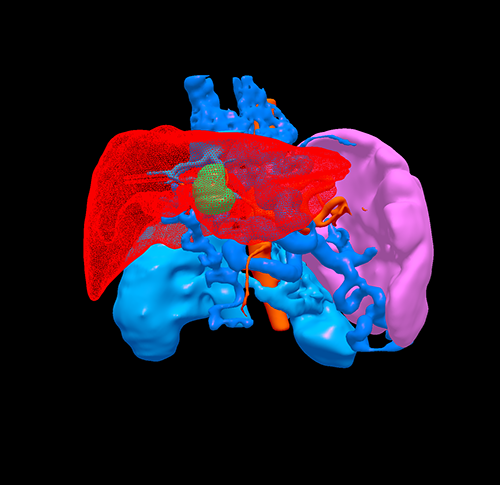

门脉高压、门静脉海绵状变、S3肝癌------S3切除、脾切除